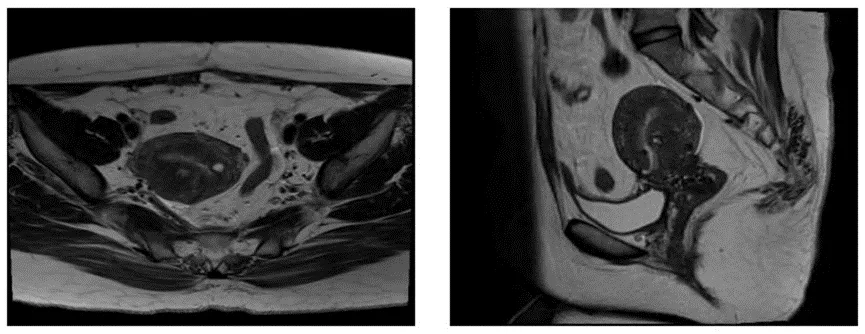

121g/L。超声提示子宫腺肌瘤可能(右后壁25mm*28mm,压迫内膜)。2022年8月MRI考虑内异症之腺肌症可能大,局部腺肌瘤形成。2022年8月5日门诊复诊时已停服炔诺酮1周,妇科检查见少量血性分泌物考虑为药物撤退性出血。 既往史:无特殊。 月经史:初潮13岁,5-7/28-30天,LMP:2022-8-5。 生育史:1-0-0-1,2020年12月剖宫产。 家族史:无特殊。 体格检查:神清,精神好,面色无苍白,心肺(-),腹软无压痛。 专科查体:外阴(-);阴道畅,内见少量淡血性分泌物;宫颈表面光,无举痛;宫体后位,饱满,质偏硬,无压痛,活动可。双侧附件区未及明显异常。 实验室检查:血常规Hb 121g/L,余项无异常;肝功能无明显异常。 影像学检查: MRI(2022-8-2):提示子宫后壁增厚,左侧壁及宫颈异常信号,考虑内异症之腺肌症,局部腺肌瘤形成可能,子宫后壁肌壁间小平滑肌瘤。 2022-8-2我院MRI影像 初步诊断:异常子宫出血,继发性痛经,子宫腺肌瘤,剖宫产个人史。 诊断依据:月经过多,经期延长伴痛经;妇科检查子宫后位,质地偏硬;超声检查及核磁共振检查提示子宫腺肌瘤。 诊治经过